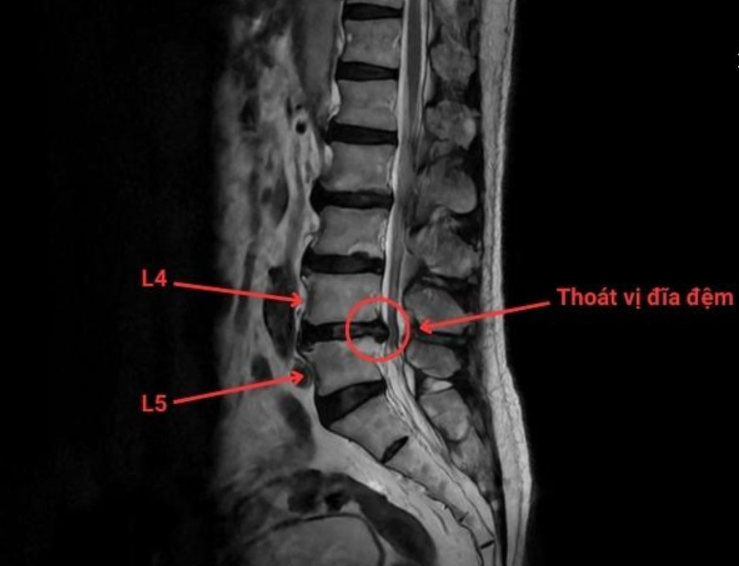

dau-dia-dem-1.png

Phim chụp thoát vị đĩa đệm cột sống thắt lưng L4/L5 - Ảnh BVCC